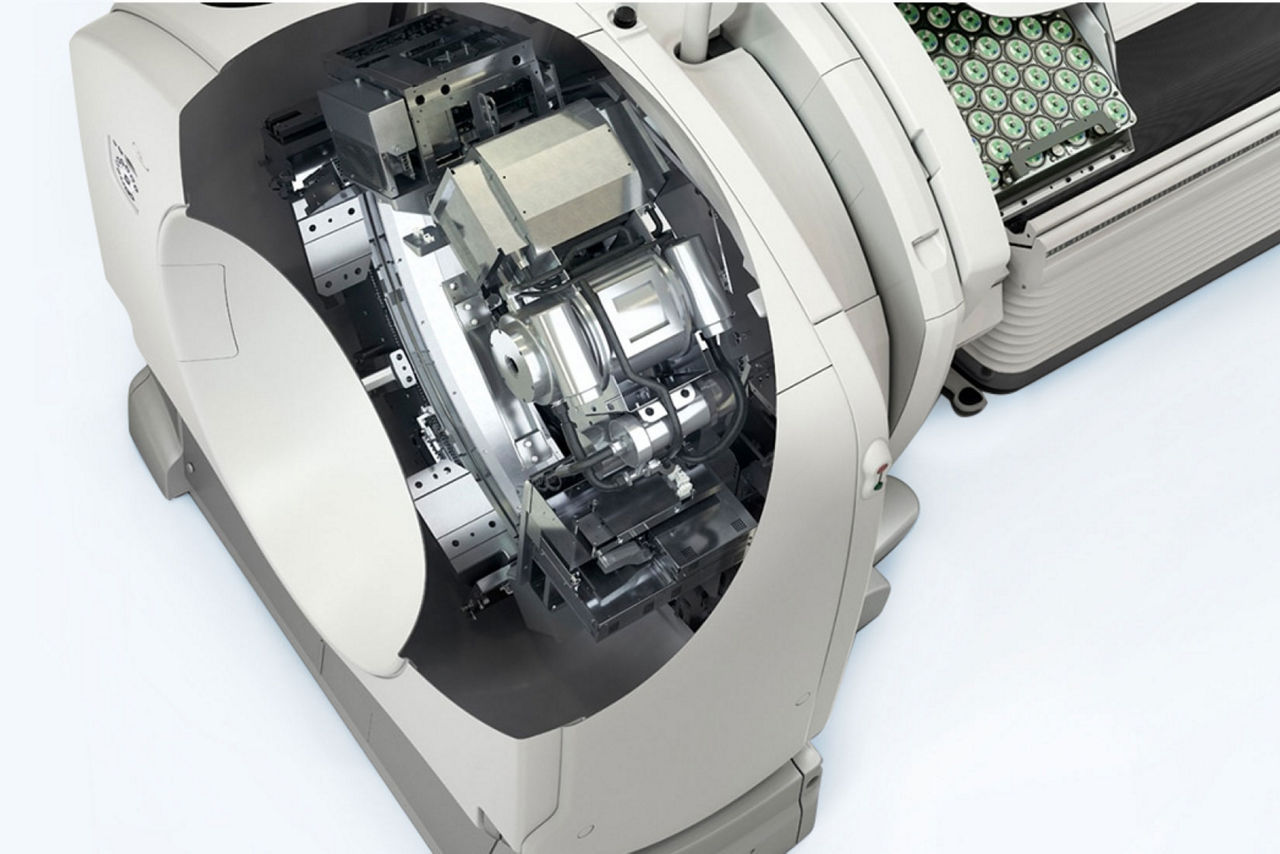

A fully digital vision for nuclear medicine

A fully digital vision for nuclear medicine

Additionally, this is a premium SPECT/CT system that delivers the added flexibility of a standalone CT that includes advancements in dose and metal artifact reduction. And it delivers the accurate, reproducible results referring physicians require in a comfortable and streamlined exam experience.